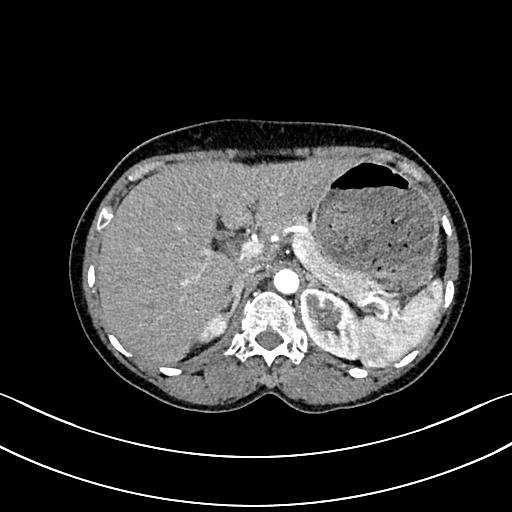

– Chụp cắt lớp vi tính ổ bụng: Hình ảnh nốt tuyến thượng thận phải kích thước 10x8mm, theo dõi thứ phát.

Hình 3: Hình ảnh chụp cắt lớp vi tính ổ bụng